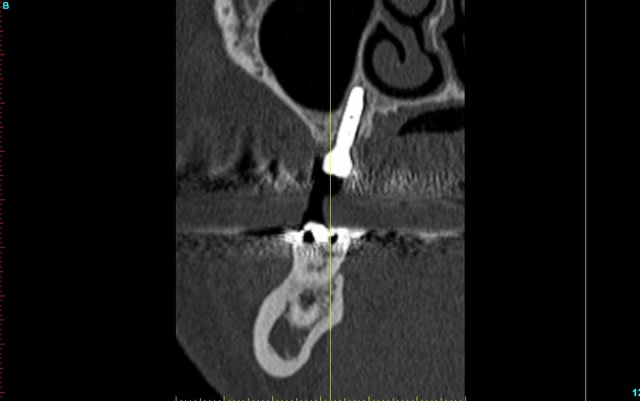

pour ceux qui m'ont demandé les images...;-)

la reconstruction 3D du scan

la planif avec le recalage du scan

la même en vue latérale avec le mapping osseux (mais qui devait merder, à cause de l'alim qui était en train de lâcher...)

et la radio post op...